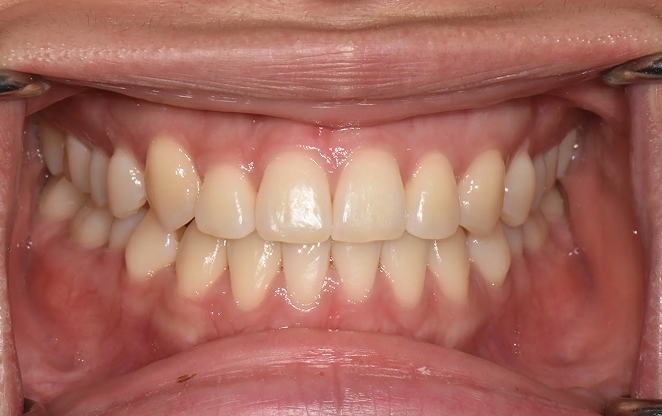

Before

After